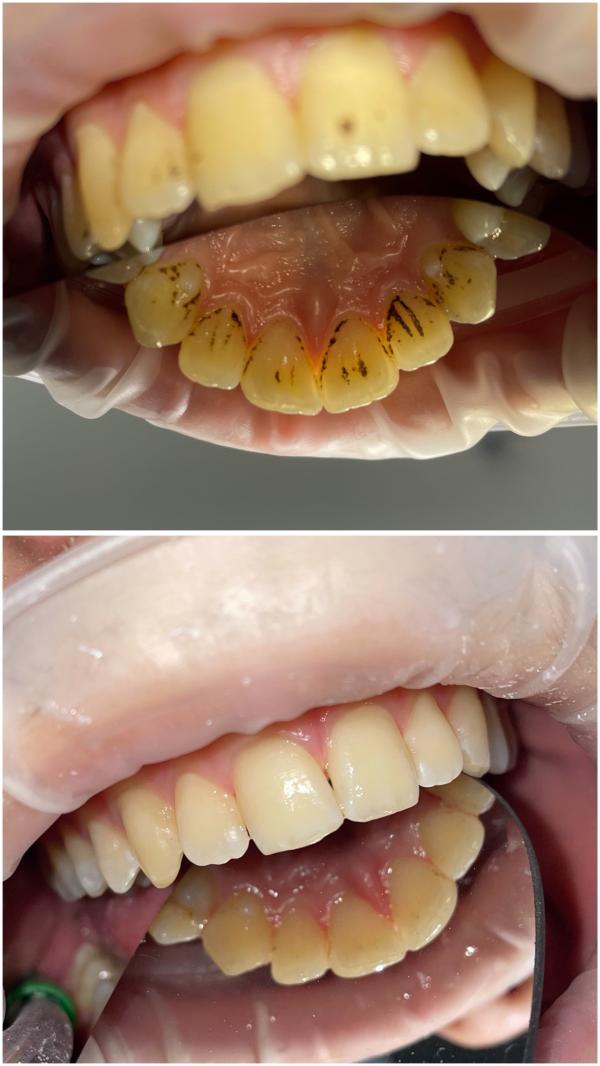

Профгигиена полости рта в Дербенте: цены для взрослых и детей

post image 1

Завтра есть окошки на профгигиену полости рта🌷🦷

Цена 2500₽

Детям 1500-2000₽